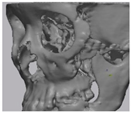

2.2. Computer-Aided Virtual Surgery, Design, and Fabrication of Patient-Specific Devices

2.5. Cone Beam CT and 3D Comparison

3.2. Fusion Rate Analysis Using 3D CT